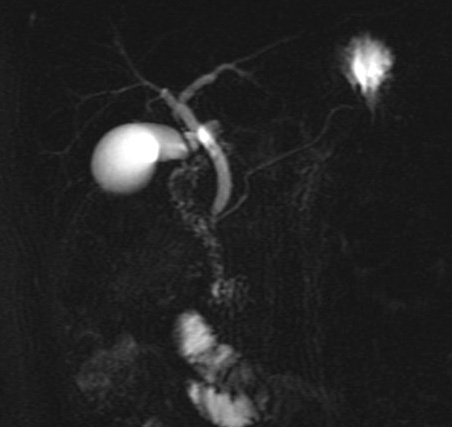

Images de

recontructional en 2D de voie biliaire intrahepatique et

extrahepatique normale . La vesicule biliaire est en

vue tres net . Duodenum D2 et D3 etre en vue .

Cholagio-IRM sequence ponderee en T2 ( Thick Slab ) |